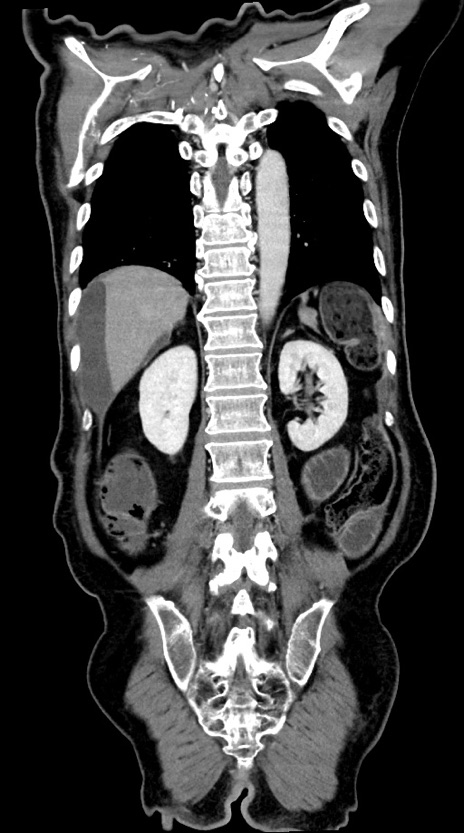

症例28(冠状断像)

【症例】60歳代男性

【主訴】嘔吐

【現病歴】胃癌にて胃全摘後。食思不振が悪化し、夜中に嘔吐することがある。

【既往歴】胃癌、胃全摘、脾摘、胆摘後

【データ】WBC 5900、CRP 10.56